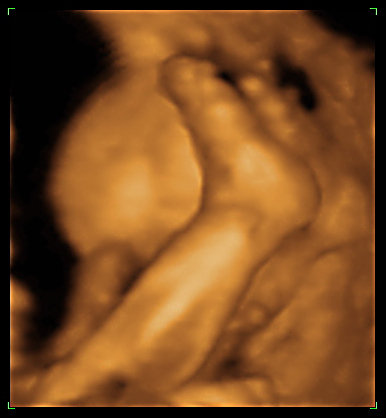

Kép Kép

No, hát ő lenne Noel baba 28 hetes nagyfiúként :) Amúgy a cukrom teljesen jó lett, nálam más miatt lehet több a magzatvíz. De azt olvastam, hogy a magzatvíz mennyisége egy napon belül is sokat változik, lehet éppen a csúcsot kapta el... Majd jövő héten kiderül mindenesetre